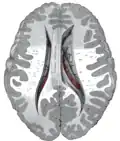

Transverse cut of brain (horizontal section), basal ganglia is blue | |